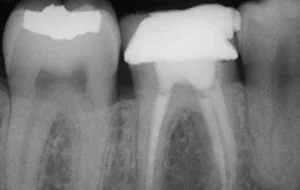

• The very first step involves an X-ray which is taken to determine the extent and approach to infection. If required local anesthesia is administered before starting the treatment.

• The next step is Cavity Preparation. A cavity is prepared, making sure all the infected tooth material or previous filling material is removed and a proper approach to inner-part of the tooth (pulp) is established.

• This is followed by disinfection and shaping of pulp canals. The infected pulp is cleared out completely, canals are shaped and cleaned. Thorough disinfection is achieved.

• Clean and disinfected canals are then sealed and filled with an inert rubber-like filling material known as Gutta-Percha.

• The very last step is restoration & crown. The crown portion of the tooth cavity is then restored with a filling, followed by a Cap/Crown cementation.